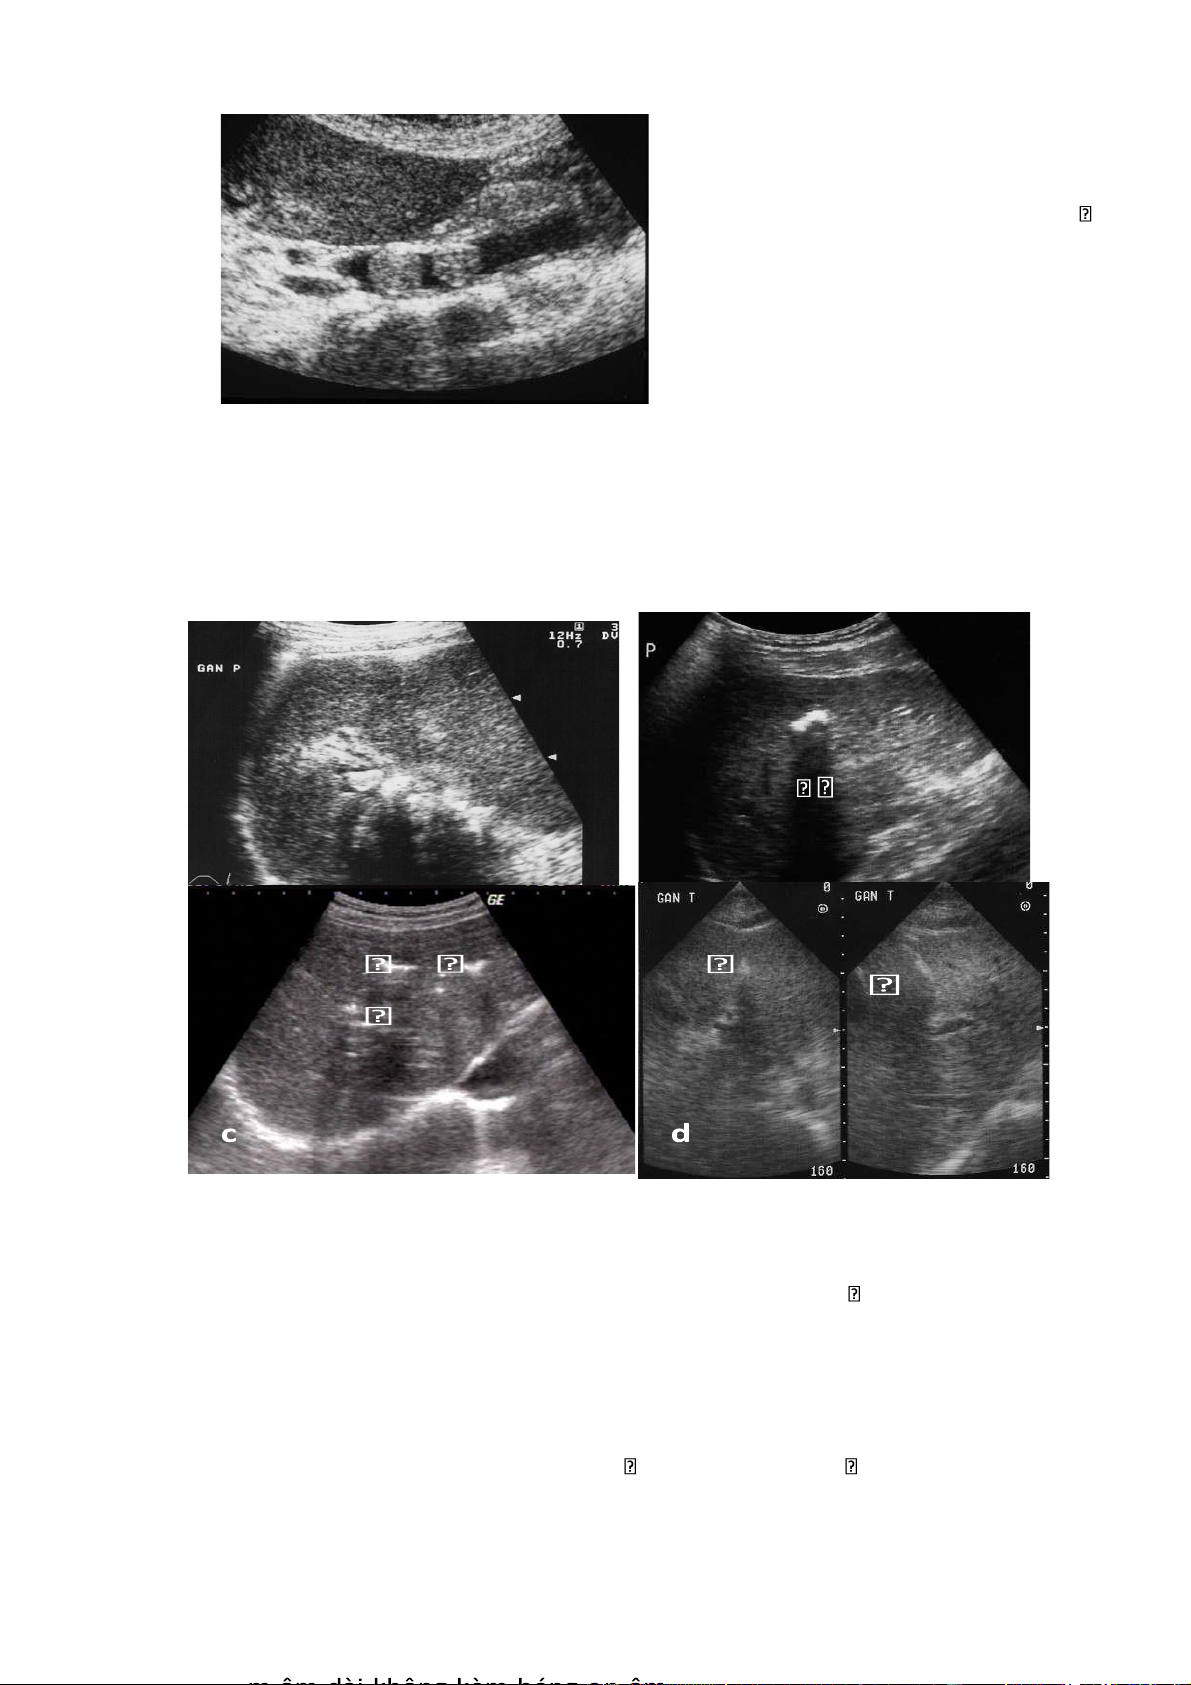

Hình 4.1 . U tế bào gan ác tính

a. Khối u tăng âm với viềm giảm âm xung quanh và hoại tử trung tâm

b. Khối u đồng âm với viền giảm âm xung quanh khối

c. Huyết khối tĩnh mạch cửa d. Di căn hạch 4.3. Di căn gan